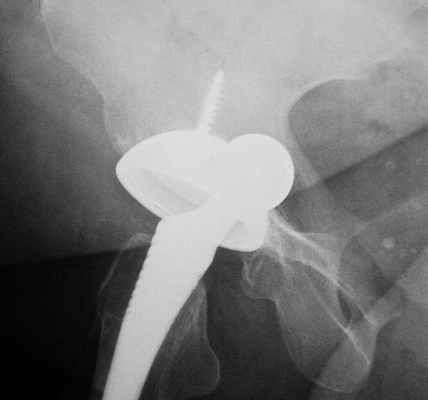

Поверхностное эндопротезирование тазобедренного сустава (McMinn) перекрывает повреждённую суставную поверхность головки бедра. Данное вмешательство является более щадящим, чем тотальное эндопротезирование и поэтому риски после него сводятся к минимуму. Во время тотального эндопротезирования хирург удаляет не только головку бедра, но и шейку бедренной кости. Принцип протеза McMinn можно сравнить с процессом установления зубной коронки. Таким образом, поверхностное протезирование сохраняет большее количество костных структур, чем полное протезирование бедра.

После поверхностного эндопротезирования сохраняется головка бедра, которая обрабатывается настолько профессионально, что хирург получает возможность установить металлический колпачок такого же размера. Искусственную вертлужную впадину, которая также оснащена скользящей поверхностью, хирург соединяет с головкой бедренной кости при помощи бесцементной методики Press-Fit.

Костная поверхность протеза McMinn пористая и шероховатая. Такая структура суставной впадины позволяет естественной кости врастать в протез на втором этапе заживления. Принцип такого бесцементного закрепления заключается в стабилизации протеза против расшатывания. Высокая нагрузочная способность поверхностного эндопротеза в большей степени адаптирована к жизни и степени активности более молодых пациентов.

Подвижность тазобедренного сустава менее ограничена, так как размеры имплантатов очень близки к оригиналу. Благодаря этому устойчивость к нагрузкам также является гораздо выше. Две высококачественные металлические поверхности вместе с синовиальной жидкостью в суставе гарантируют низкий износ и высокую стойкость.